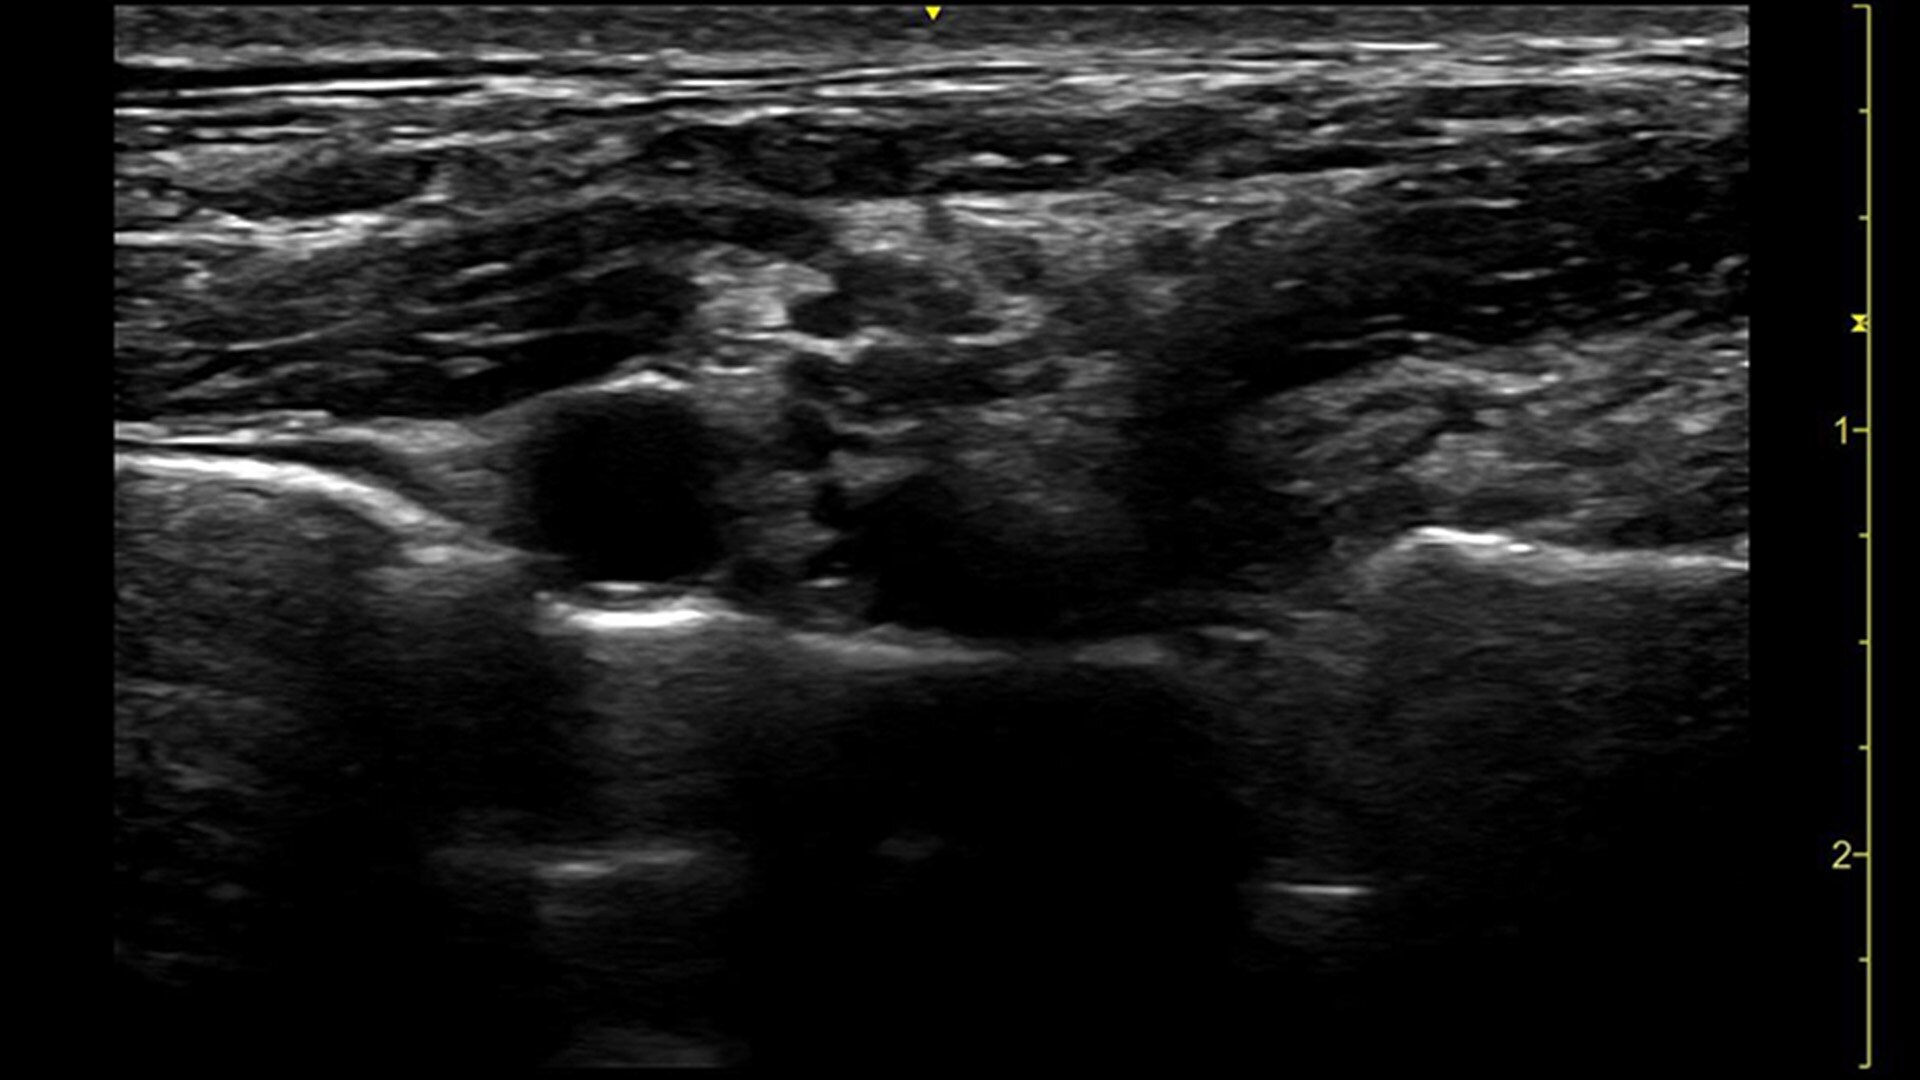

症例が複雑になれば、それだけ不確実な要素も伴います。だからこそ重要になるのは、いかに早期発見し、早期治療に専念できるかどうか。一手先を読み、よりよい未来を的確に見抜く先生方の日々の診断を、Voluson Expert 22の卓越した画質と独自のクリニカルツールがサポートします。

胎児心臓の異常を早期に検出することで、より迅速な介入、分娩計画、予後改善が見込まれます。Voluson Expert 22では、スクリーニング・診断・モニタリングまでトータルにサポートする多彩なツールを取り揃えています。